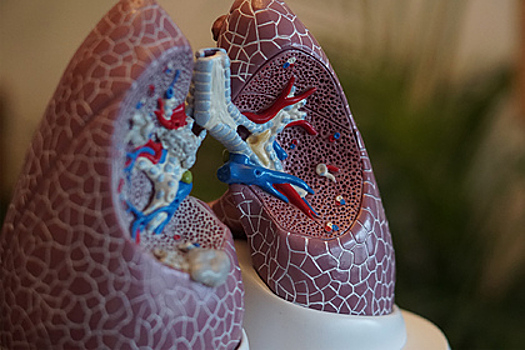

Российские специалисты из Национального медицинского исследовательского центра трансплантологии и искусственных органов (НМИЦ ТИО) имени академика Шумакова разработали технологию, позволяющую сохранять качество донорских легких вне тела до восьми часов. Об этом сообщает «Газета.Ru» со ссылкой на главу центра Сергея Готье.

Как уточняется, технология основана на погружении органа в специальный перфузионный раствор. Поскольку легкие — крайне нежный орган, подверженный отеку мембран, необходимо использовать должный уровень сохранности.

Обычно используется контейнер, обеспечивающий циркуляцию раствора для очищения от продуктов распада и поддерживает работоспособность клеточных мембран. В новой работе специалисты научились сохранять кислородопроводящую функцию легких до восьми часов.